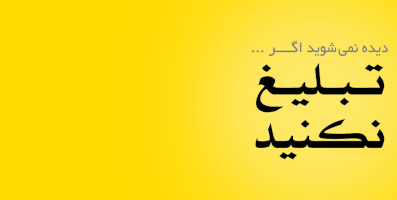

قبل از بررسی نشانهها، خوب است درک پایهای از نحوه پمپاژ خون توسط قلب داشته باشیم. قلب را بهعنوان یک پمپ چهارحفرهای تصور کنید. خون از بدن به دهلیز راست بازمیگردد، سپس به بطن راست میرود که آن را به ریهها پمپ میکند تا اکسیژن دریافت کند. پس از آن، خون غنی از اکسیژن به دهلیز چپ و سپس به بطن چپ میرسد. بطن چپ بخش قدرتمند قلب است؛ این بخش خون را به سراسر بدن پمپ میکند. این سیستم، اگر عضله قلب ضعیف شود، اگر مقاومت زیادی وجود داشته باشد (مانند فشار خون بالا)، یا اگر دریچهها درست کار نکنند، میتواند ناکارآمد شود. وقتی قلب نتواند خون را بهطور مؤثر پمپ کند، مایعات میتوانند تجمع پیدا کنند و علائم مختلفی ایجاد کنند.

• تنگی نفس: این یکی از نشانههای مهم است. بسیاری فکر میکنند فقط تناسب اندام ندارند یا پیر شدهاند. اما اگر سمت چپ قلب ضعیف شود، مایع میتواند در ریهها جمع شود (ادم ریوی). این باعث میشود تبادل اکسیژن در ریهها سخت شود، مثل این است که زیر آب نفس میکشید. توجه کنید که این با حمله قلبی، که یک انسداد ناگهانی است، متفاوت است.

• تورم در پاها، مچ پا و ساقها (ادم): این تورم اغلب نشانه نارسایی سمت راست قلب است. اگر سمت راست قلب نتواند خون را بهطور مؤثر به ریهها پمپ کند، مایع میتواند در قسمتهای پایینی بدن جمع شود. این معمولاً در مراحل بعدی، پس از مشکلات سمت چپ قلب، رخ میدهد.

• تورم شکم (آسیت): این معمولاً نشانه نارسایی سمت راست قلب است. وقتی سمت راست قلب نتواند خون را بهطور مؤثر پمپ کند، فشار افزایش مییابد و مایع در حفره شکمی جمع میشود، که میتواند باعث تورم شکم و فشار بر اندامهای داخلی شود.